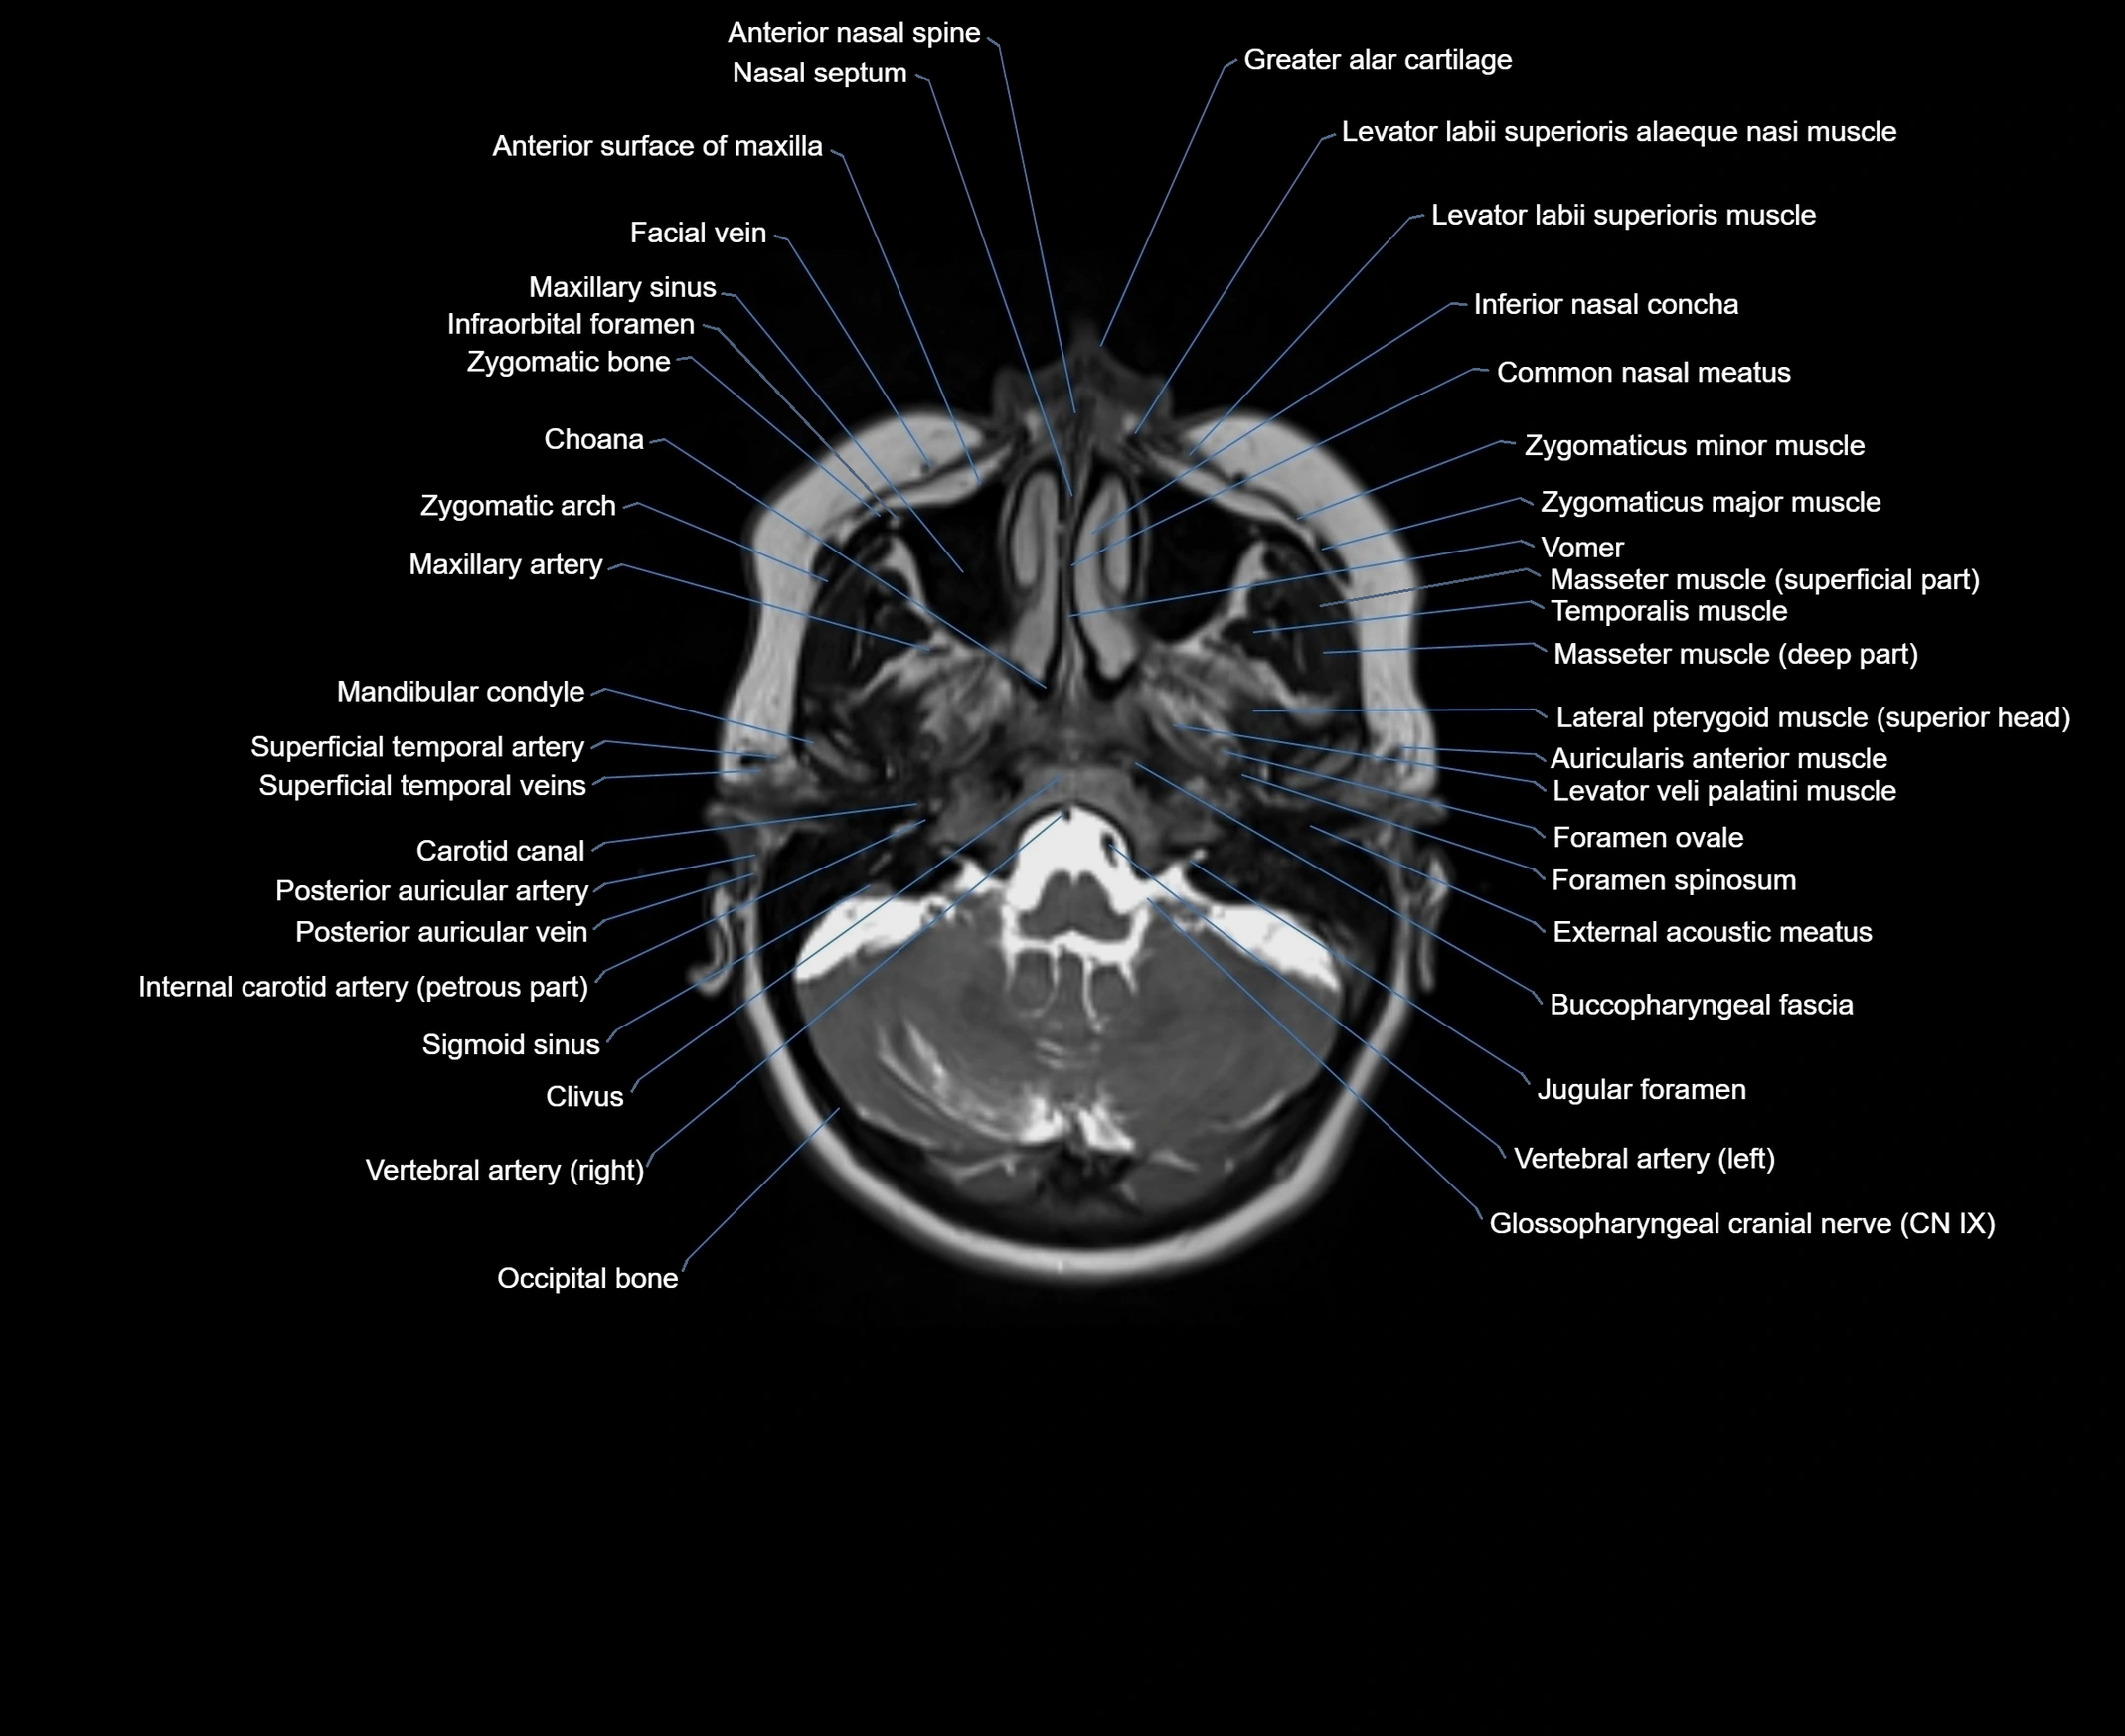

- Buccopharyngeal fascia

- Carotid canal

- Choana

- Clavicle

- Common carotid artery

- External acoustic meatus

- Foramen ovale

- Foramen spinosum

- Glossopharyngeal nerve (Cranial nerve IX)

- Jugular foramen

- Mandibular condyle

- Maxillary artery

- Neck of rib

- Occipital bone